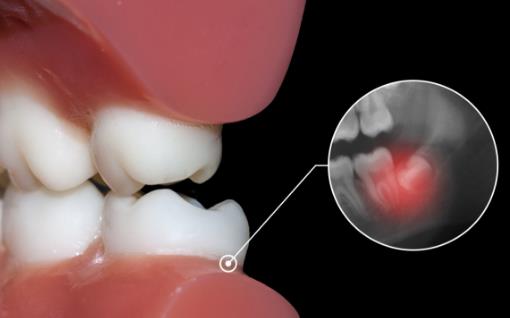

智齿的位置不合适,很难长出来。如果智齿的位置不合适,需要对牙床或者其他牙齿进行破坏,那这个过程是非常痛苦的,而且,这种智齿也是很难长出来的,在长智齿的过程中因为破坏了牙床,很容易引起一些牙齿的炎症或者是牙周的炎症,甚至还可能引发高烧等症状。对于这种情况,一定要去医院进行治疗,消除炎症,缓解疼痛,等到智齿长出来之后立即进行拔除。

2.侵犯邻牙:通常患者不自知,而由牙医以X光诊断得知。通常智齿萌发的空间不足,而会倒在第二大臼齿上,因而造成第二大臼齿清洁不易,甚至是牙齿部分吸收的现象,造成患者不舒适或牙疼。

6.阻生齿:通常这是最讨厌的一种,牙医会觉得很难搞定,但病人却不一定有感觉,因此忽略了。这一种类型的牙齿,通常埋在齿槽骨的里面,如果会痛,或是诊断会有病灶发生的时候,就需要拔除了。